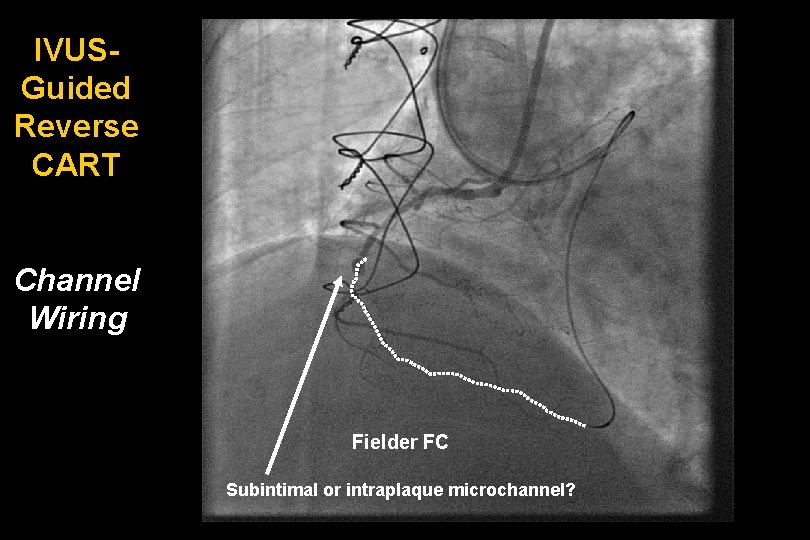

IVUSGuided Reverse CART Channel Wiring Fielder FC Subintimal or intraplaque microchannel?